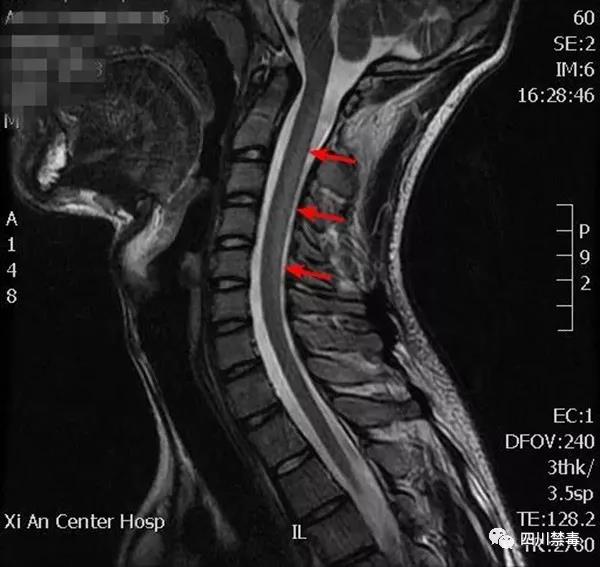

中国消费者报公号报道,上个月,陕西西安市中心医院神经内科连续收治两例特殊的大学生脊髓病患者。据了解,如若任其发展,可能面临瘫痪或截肢。而经诊断发现,致其患病的罪魁祸首居然是“笑气”。

两位患者均为在校大学生,在入院前2周出现了双手抖动、双足趾末端麻木、双腿行走不稳、乏力等症状。最终,医院怀疑两人得了同样的疾病——B12缺乏导致的脊髓亚急性联合变性。

两名大学生为何患上同一种疾病? 在西安市中心医院神经内科主管医生陈筱山耐心的沟通、问诊和查体之后,两位大学生患者最终陈述了1年来频繁出入酒吧,购买吸食笑气的特殊病史。